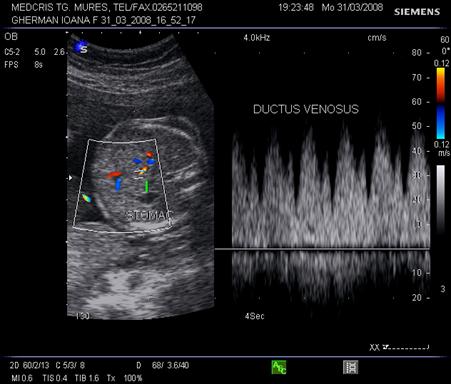

Ductul venos

In sectiune sagitala ductul venos apare ca o continuare a venei ombilicale spre vena cava inferioara. Inclinatia creste de la 7 la 48 la locul de unire cu vena cava. Aspectul este de "trompeta" de la circa 17 saptamani.[14,17]

Fig.nr. 328. Schema ductului venos( cu doua sageti, sageata unica indica directia fluxului sangvin,adaptat dupa Mihu[17] )

Aspectul eco Doppler normal in ductul venos este de sistola ventriculara, diastola ventriculara, contractie atriala, deci aspect trifazic.

Ductul venos creaza o comunicare intre sistemul venos periferic ombilical si sistemul venos central al fatului. Gradientul presional in ductul venos se modifica in caz de suferinta fetala.

Daca are loc centralizarea circulatiei, prin scaderea presiunii venoase centrale, scade presiunea in ductul venos in timpul contractiei atriale, cu aparitia reverse - flow.( unda a negativa ) [19]

Fig. nr.329. Ductus venosus( sageata ) la o sarcina de 16 sapt,. sectiunea sagitala fetala

Fig. nr. 330. Ductus venosus la doppler pulsat cu CFM , la o sarcina de 27 sapt. Se remarca aspectul normal trifazic al undei .

Fig. nr. 331. Ductus venosus la doppler pulsat si CFM , la 21 sapt, fat in sectiunea transversala a stomacului